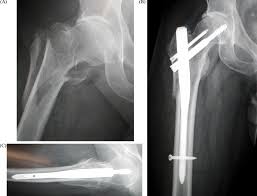

sebabnya ialah... lihat gambar dibawah..

mcam mana?

ada rasa gerun tngok ni?

tu la sbab operation..

nak masukkan besi kerana tulang peha kiriku patah..

ataupun left femur..